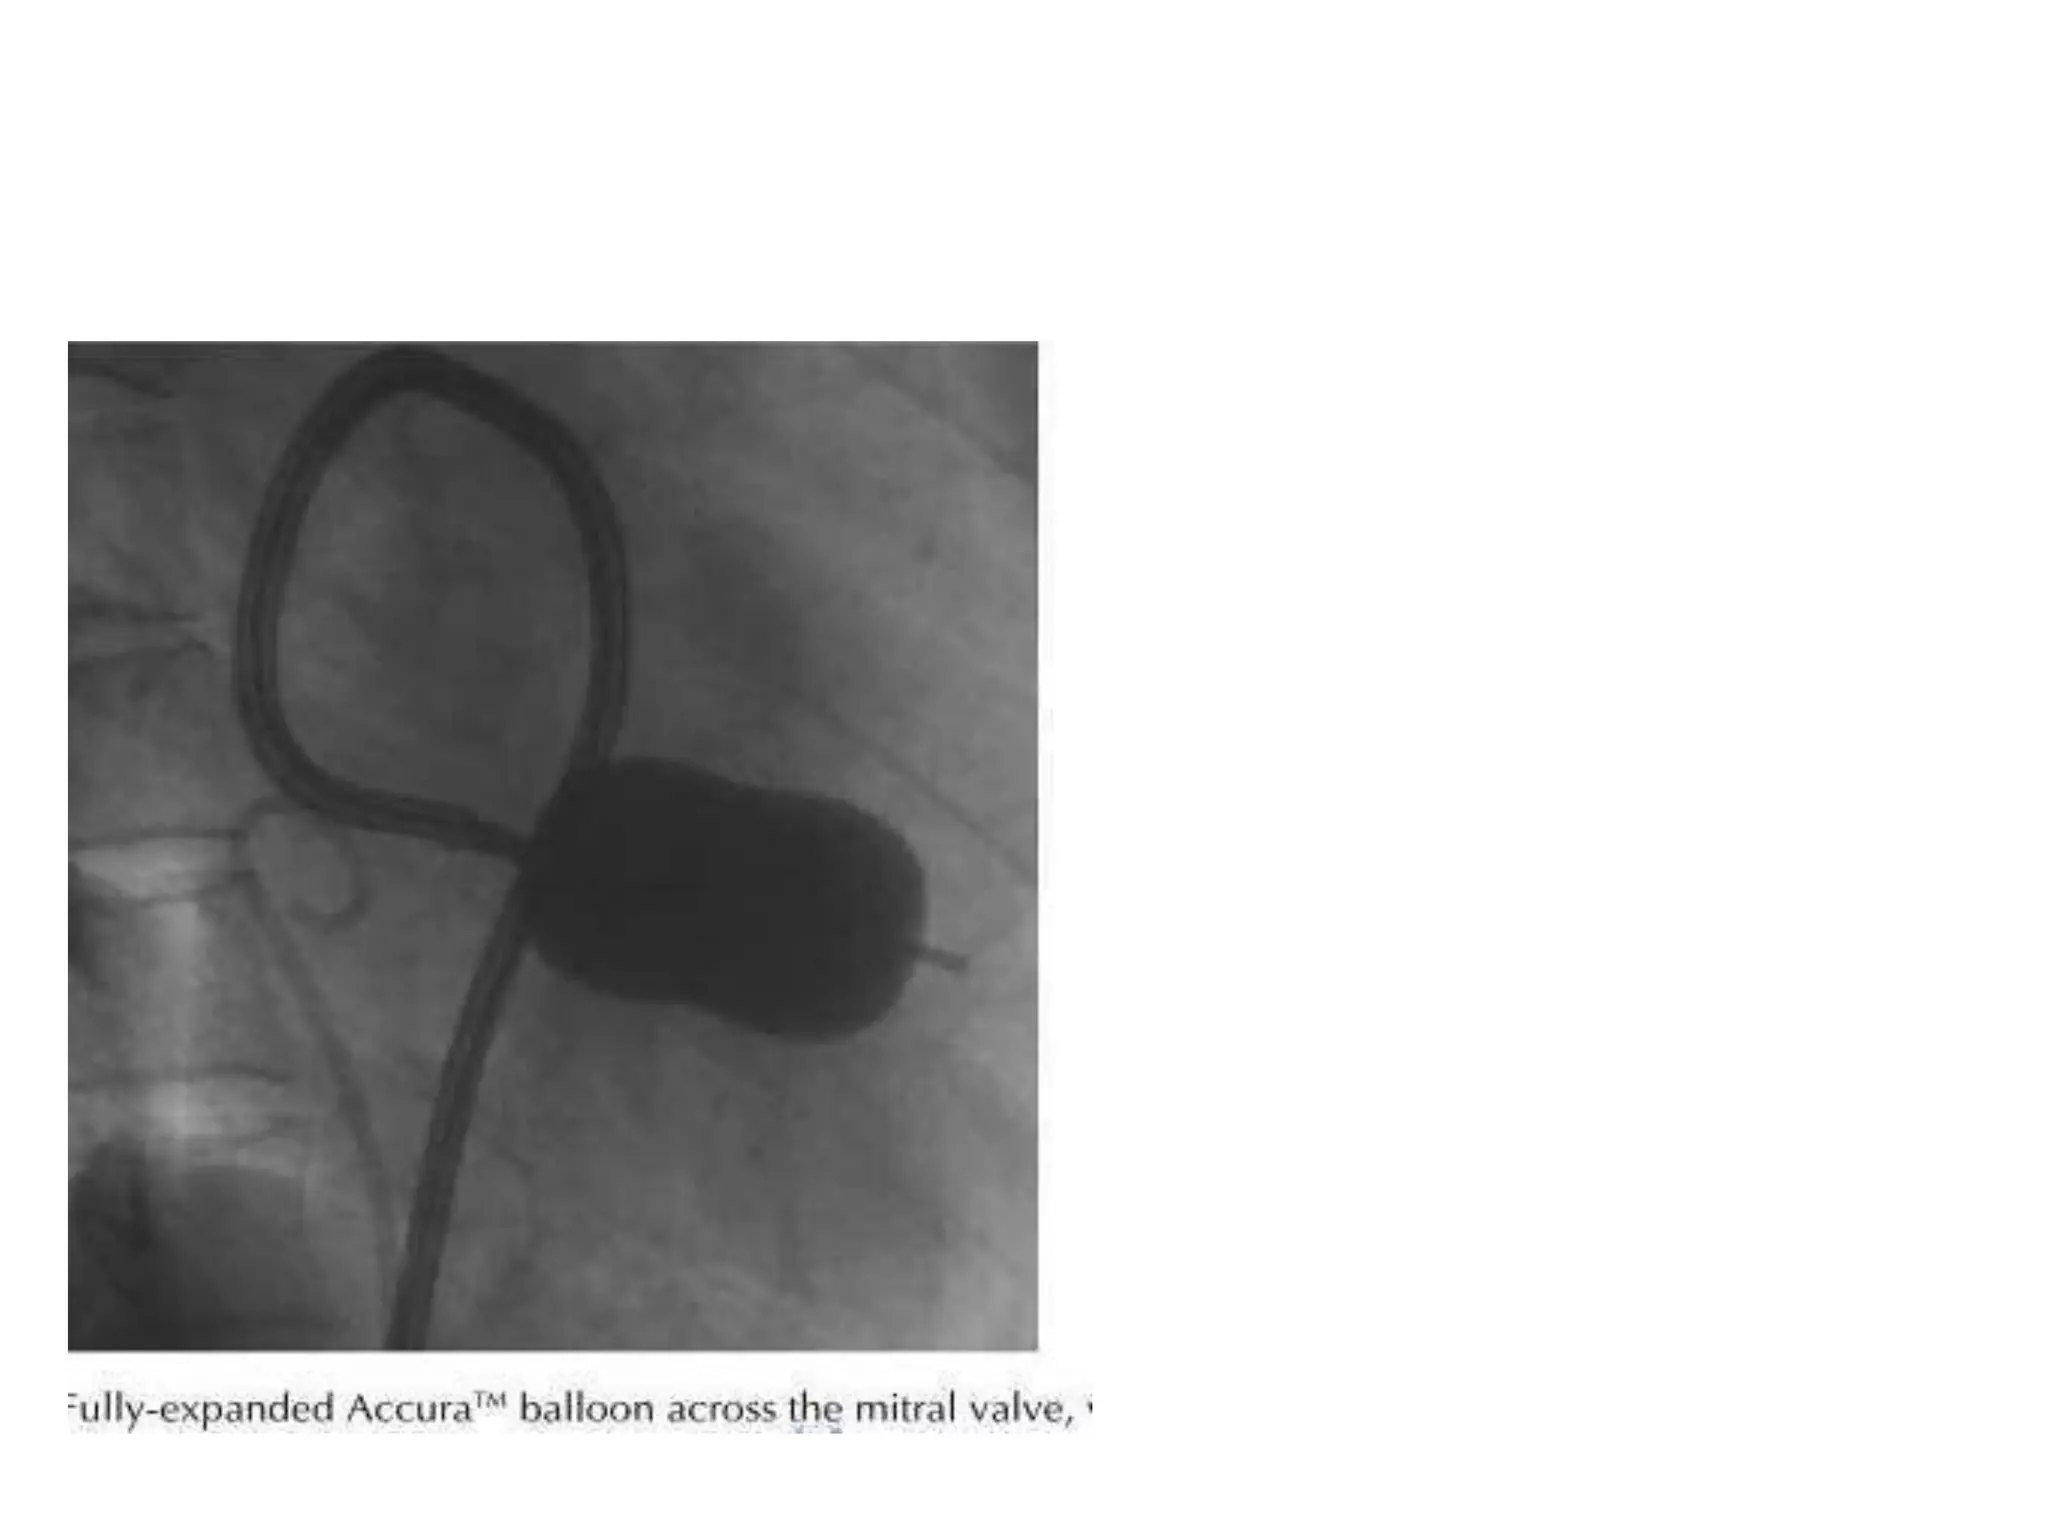

Fully inflated PMV balloon across MV in RAO view. Note the alignment of long axis of

balloon catheter along the long axis of LV cavity

Fully inflated PMVballoon across MV in RAO view. Note the alignment of long axis of balloon catheter along the long axis of LV cavity